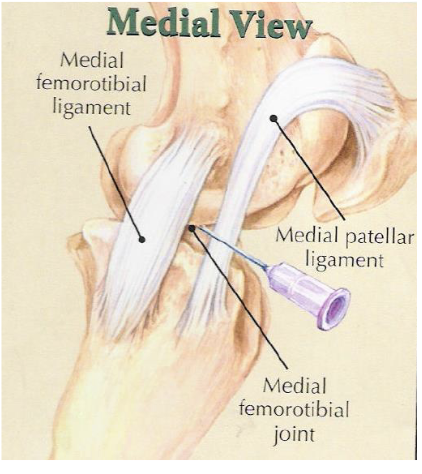

stifle

bones- patella, distal femur (+ medial and lateral trochlear ridges), tibia

lateral trochlear ridge of femur is shorter and smaller than medial

soft tissue structures- 3 patellar lig (medial middle lateral), medial & lateral collateral lig

joints- femoropatellar, medial femorotibial, lateral femorotibial

what is desensitized with a femoropatellar joint block

joint, in 65% of horses it can communicate w/ medial femorotibial joint but youre never sure which horses so you treat them all separately

what is desensitized with a medial femorotibial joint block

joint, +/- communication w/ femoropatellar joint in some horses

what is desensitized with a lateral femorotibial joint block

joint